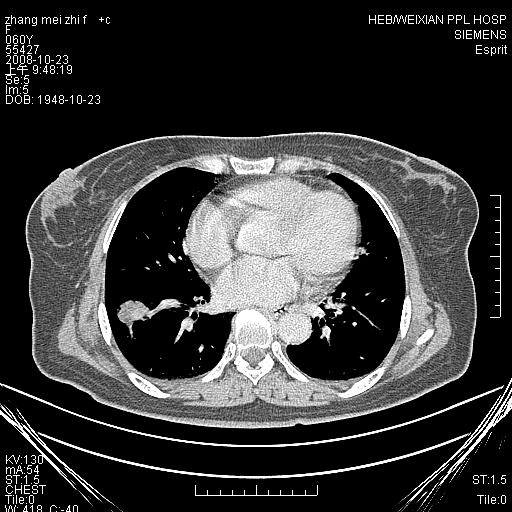

体检发现肺部肿块,现无不适。五年前曾有过哮喘病史。

强化扫描后病灶几乎无增强,强化后的病灶看起来密度虽高,是我为了清晰改变了窗宽窗位。(有点弄巧呈拙)

先对现有的图象资料谈几点看法:病变位于右肺下叶前基底段,上部呈类圆形改变,分叶及毛刺征象不明显,下部呈不规则气腔改变,近肺门侧可见与一粗大血管相连,考虑为引流静脉影.其他肺叶相对正常所见.分析:该病灶良恶性均有可能.(现有资料来说).强化及穿刺活检有助鉴别.

考虑右肺下叶前基底段周围型肺癌可能性大。

右肺下叶前基底段占位性病变,不排除周围型肺癌可能,尽快手术为妙。

术后冰冻切片怀疑是细支气管肺泡癌,等病理结果。